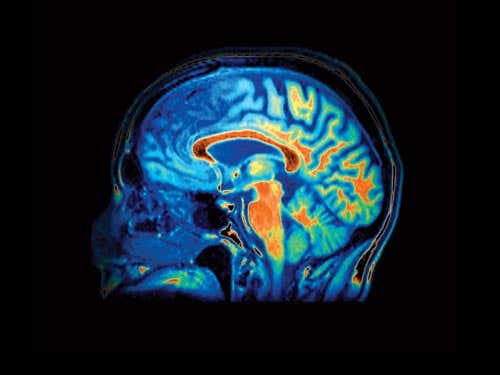

A hole in the skull could increase blood flow to the brain (Image: Zephyr / SPL) Terry Pratchett wearing the laser helmet. After Pratchett was diagnosed with Alzheimers in 2007, he wore this helmet in the hope that it would help repair brain cells by penetrating the skull with light (Image: RDF Media)